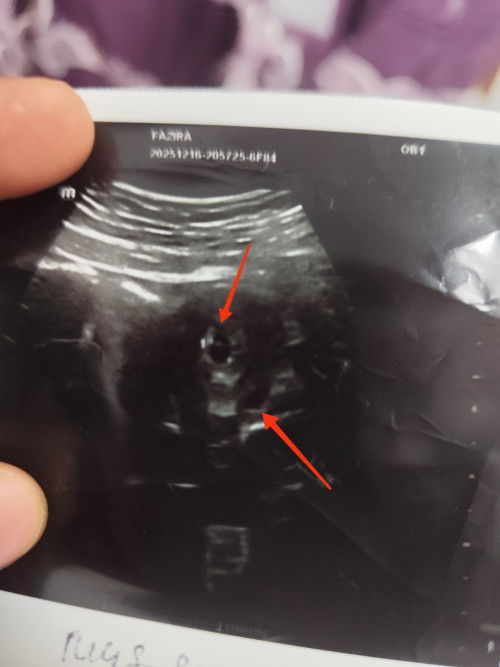

Adakah itu kembar?sy scan semlm....dokter pon x pasti...boleh mommy bgi pendapat..?

Adakah itu kembar?

Berapa weeks awak? Repeat scan lagi 2 minggu